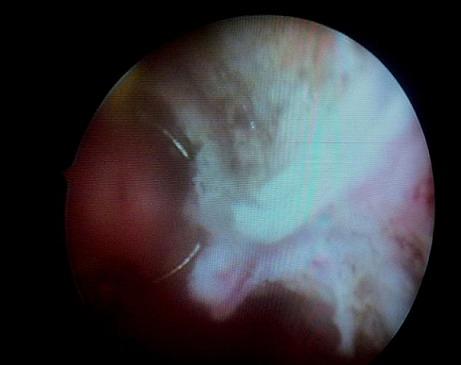

Bladder schwannomas are exceedingly rare, benign or malignant, nerve sheath tumors that are most often discovered in patients with a known diagnosis of Neurofibromatosis type 1 (NF1). A few sporadic case reports of bladder schwannoma have been published in urologic, obstetric/gynecologic, and pathologic journals. We report a case of an isolated schwannoma of the urinary bladder. To our knowledge, this represents only the sixth case of benign schwannoma of the urinary bladder in a patient without von Recklinghausen disease.

膀胱神经鞘瘤极为罕见,是一种良性或恶性的神经鞘肿瘤,最常出现在已确诊为1型神经纤维瘤病(NF1)的患者中。泌尿外科、妇产科和病理学杂志上已发表了几例膀胱神经鞘瘤的散发病例报告。我们报告一例孤立性膀胱神经鞘瘤病例。据我们所知,这是仅有的第六例在无冯雷克林霍增氏病患者中发生的膀胱良性神经鞘瘤病例。